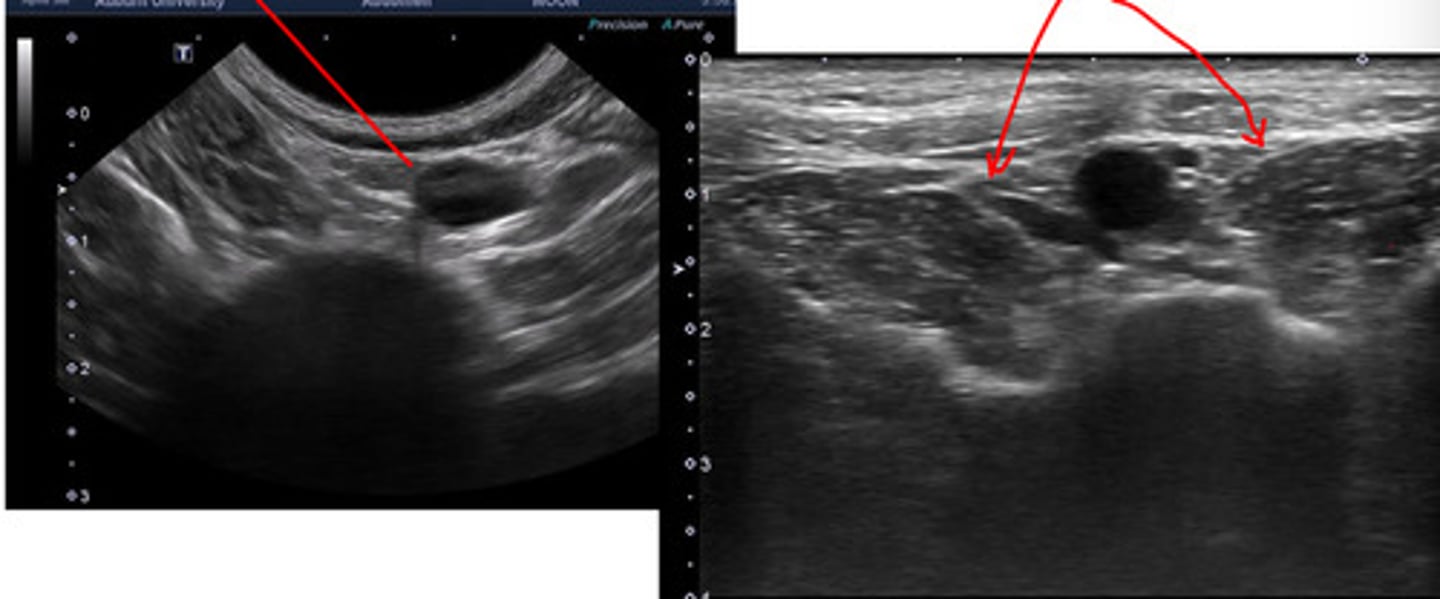

reactive or neoplastic

lymphadenopathy can be _____ or ______

metastatic

reactive lymphadenopathy is __________

hypoechoic

neoplastic lymohadenopathy is hyperechoic or hypoechoic?

increases size

lymphadenopathy causes what in regards to size?

irregular margination

lymphadenopathy causes what in regards to margination?

left- neoplasia

right- normal/reactive

which medial iliac ln. is neoplastic and which is normal/reactive?

normal

a reactive medial ln. is normal or abnormal?

lymphoma

which abnormality is this?